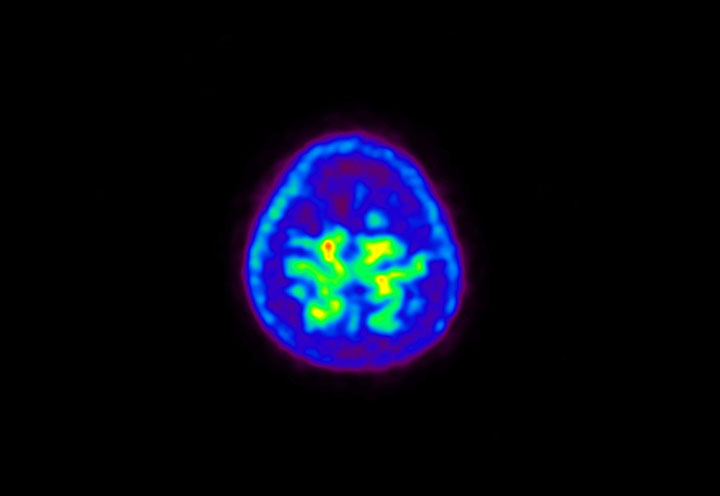

Head / Case5 : Amyloid

Courtesy : Kindai University Hospital

- Imaging protocol

- Injected dose: 4.27 MBq/kg, 18F-Flutemetamol

- Uptake time: 99 minutes

- Scan time: 20 minutes